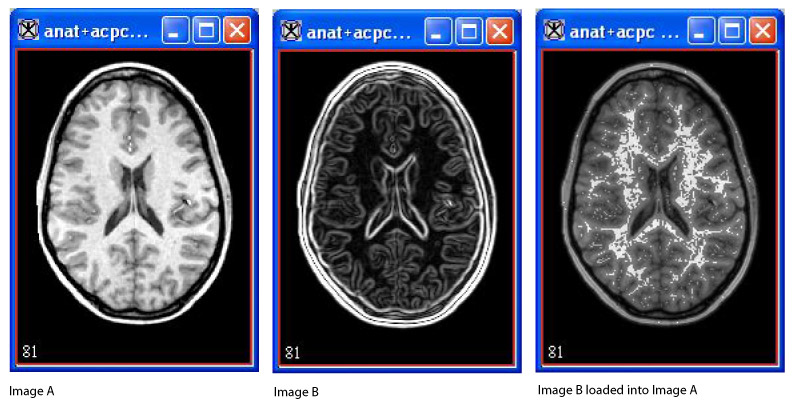

The triplanar-dual view displays two image datasets (referred to as Image A and Image B) and a blended version of both Image A and Image B from three orthogonal planes.

1 Open two 3D or 4D images, which become known as Image A and Image B.

2 Load Image B into Image A.

3 Select Image > Views > Triplanar-Dual. The triplanar-dual view appears in an image window.

Figure 1. Image A, Image B, and Image B loaded into Image A